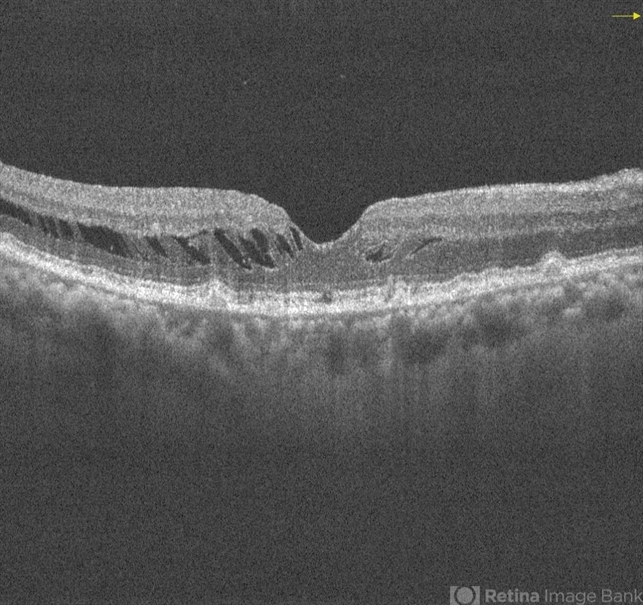

- drusenoid deposit, vitreomacular traction (VMT)

- Right eye one month post-operative OCT showing VMT release with return of the foveal depression and good vision. There is marked reduction in intra retina schisis and preserved outer retina layers.